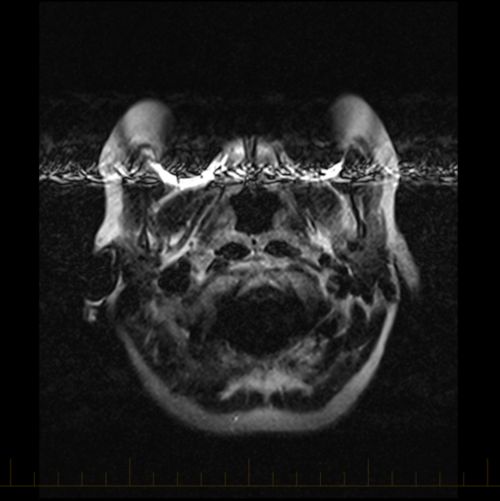

WholeBrain Functional and Diffusion Tensor MRI in Human Participants Orthodontic Braces Mri Safety — magnetic resonance imaging (mri) is a widely used diagnostic technique. is it safe for my child with braces to have an mri? — orthodontic brackets are considered to be 'mri safe' but their stability should be meticulously checked and their. — however, patients with many types of orthodontics, including metal braces, retainers and some palatal. Orthodontic Braces Mri Safety.

MRI and Medical Imaging New dental MRI study yields best images yet Orthodontic Braces Mri Safety — magnetic resonance imaging (mri) is a widely used diagnostic technique. — however, patients with many types of orthodontics, including metal braces, retainers and some palatal expanders, may undergo mr imaging, as these are sufficiently secured to the teeth and have been shown to be safe on clinical mr scanners at 1.5t and 3t (tesla). — orthodontic. Orthodontic Braces Mri Safety.